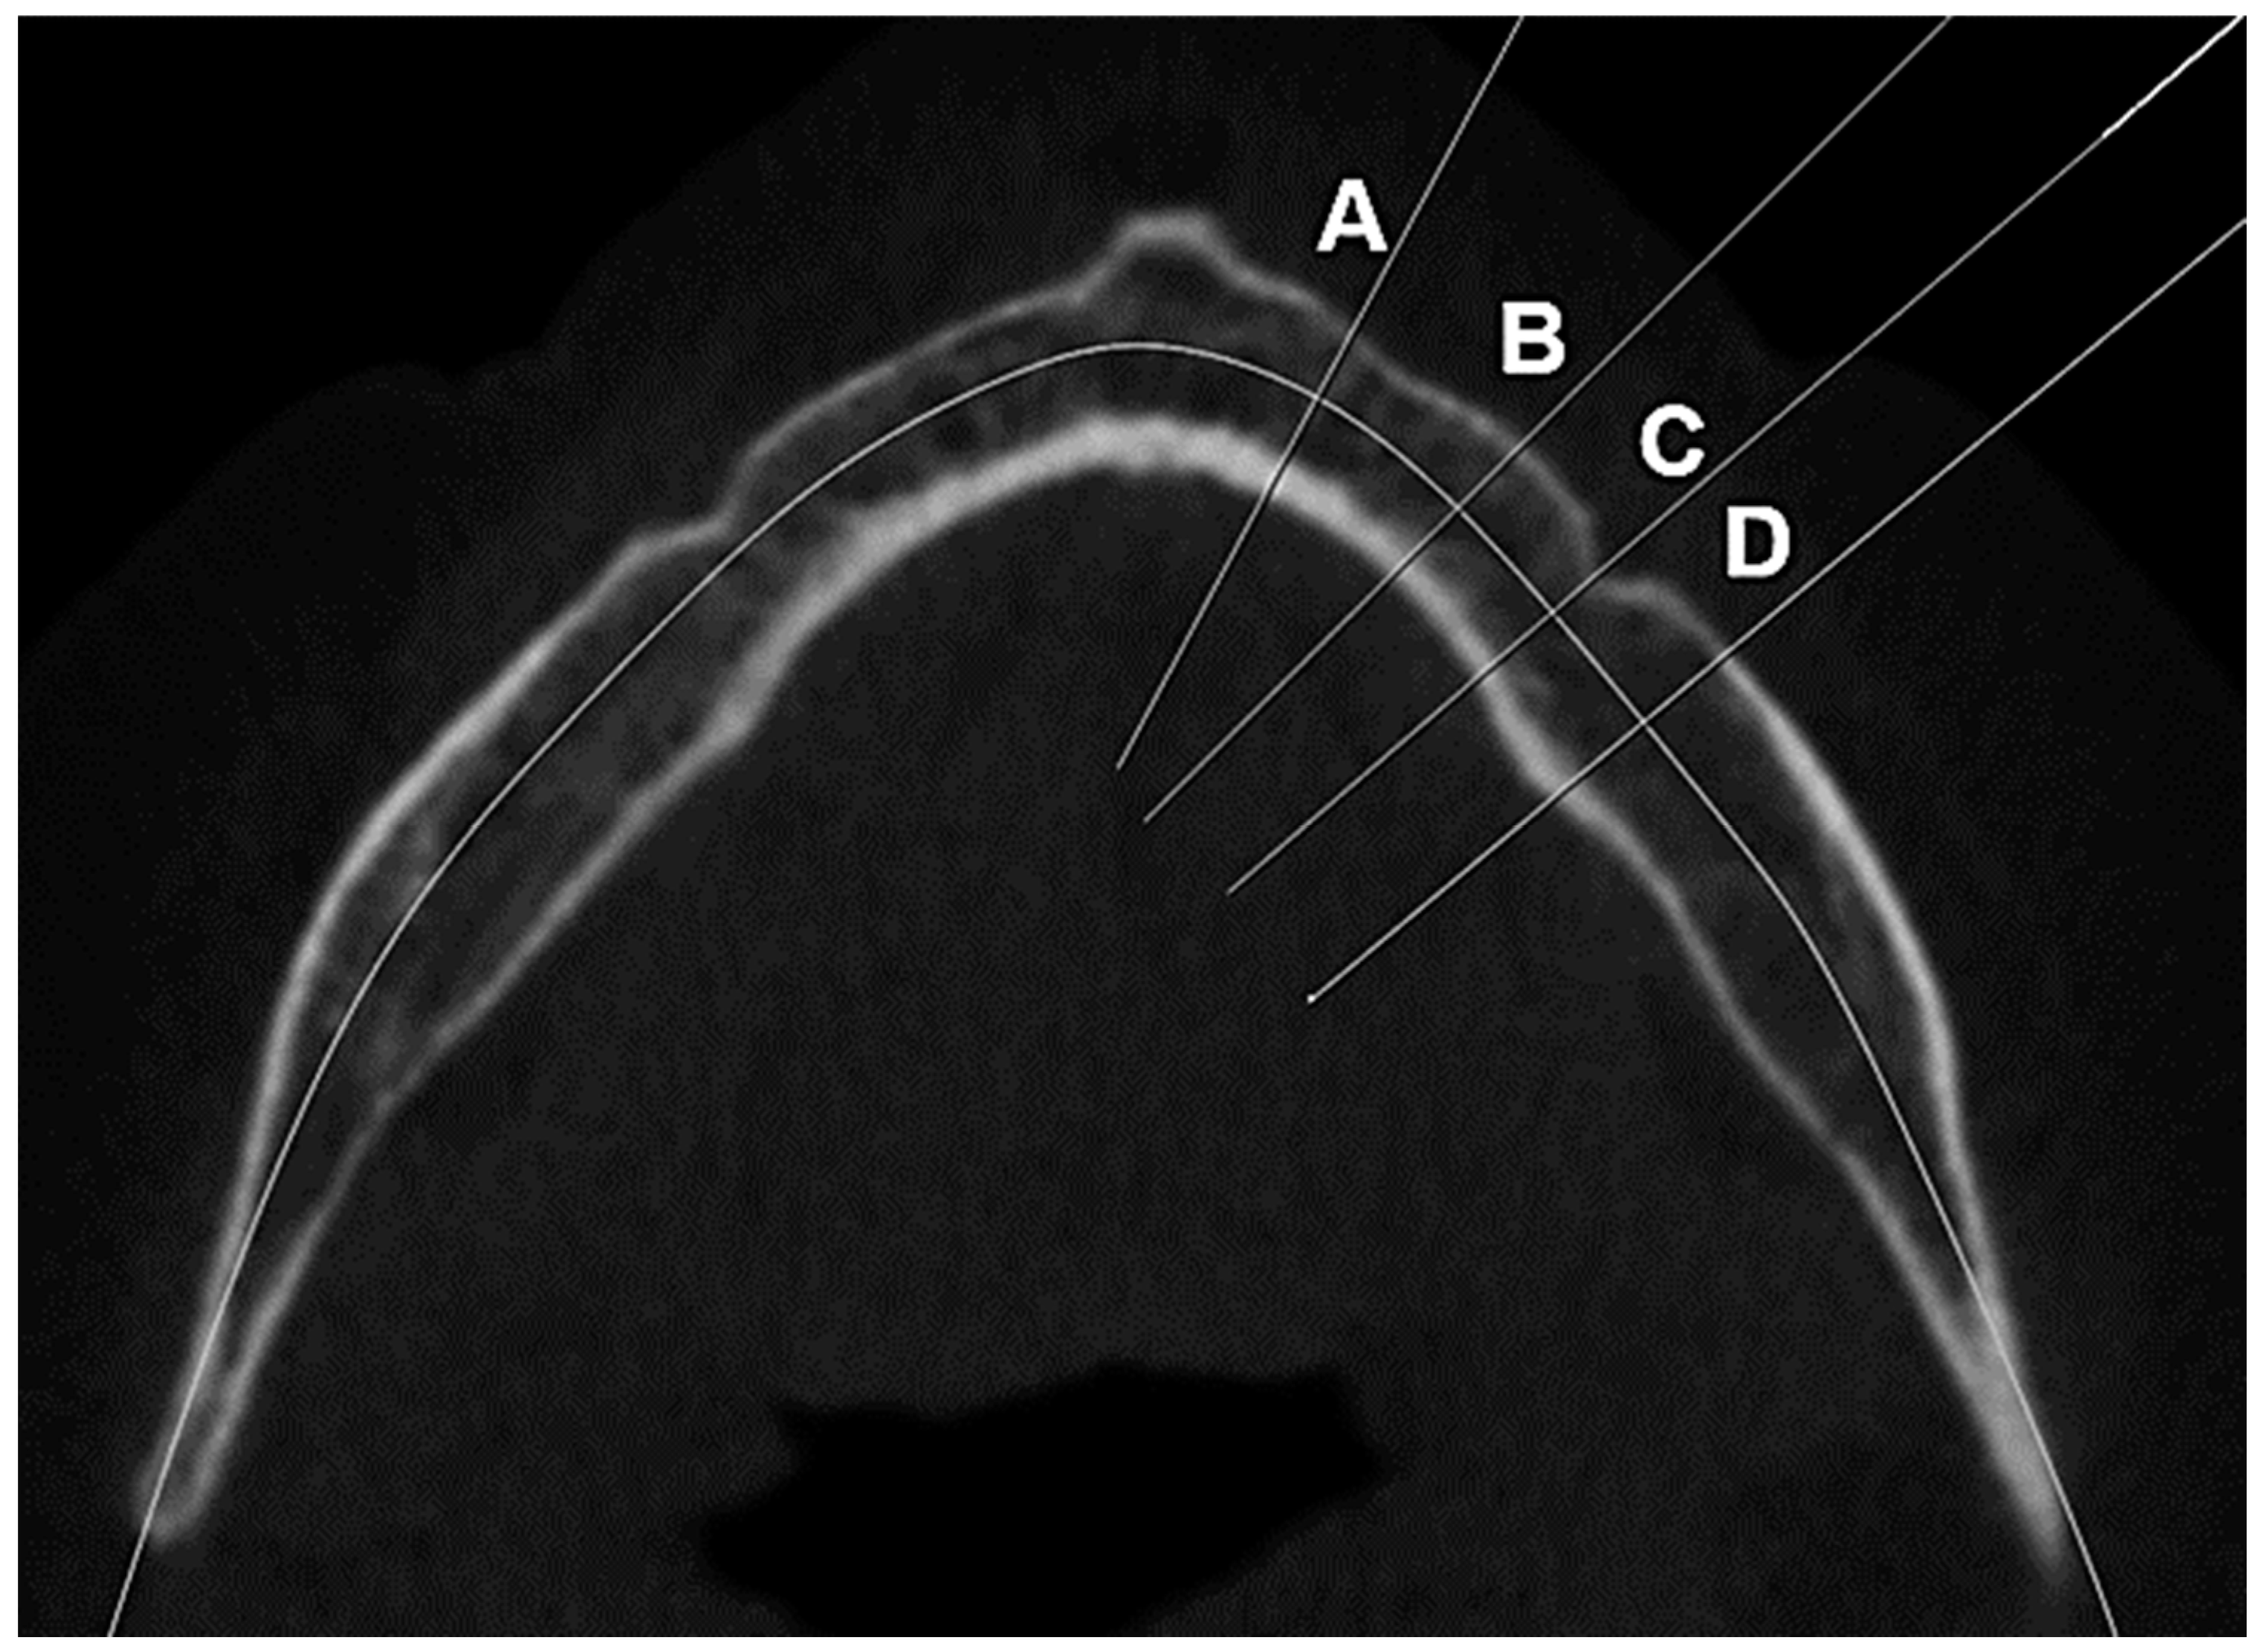

2.3.2. Cortical Bone Thickness

2.3.3. Determination of the Computed Tomography Cortical Index (CTCI)